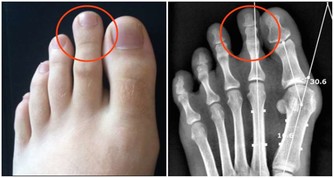

人體約有600-700個淋巴結,分佈於人體的各個地方。一般來說,淋巴結在淺表的位置才會被觸及到,例如,頸部、鎖骨上窩、耳後、腋窩、腹股溝等部位。這些位於人體淺表的淋巴結很小,直徑約2-2.5毫米,質地柔軟、光滑可移動、沒有壓痛感。如果淋巴結突然改變了性質,例如變大、疼痛、質地變硬、不光滑、與周圍組織粘連,那麼就說明淋巴結出現了病變。

②惡性腫瘤淋巴結轉移,已經出現癌細胞轉移的淋巴結,質地比較硬,表面會有凹凸不平的樣子,還會和皮膚發生粘連,一般沒有疼痛感;